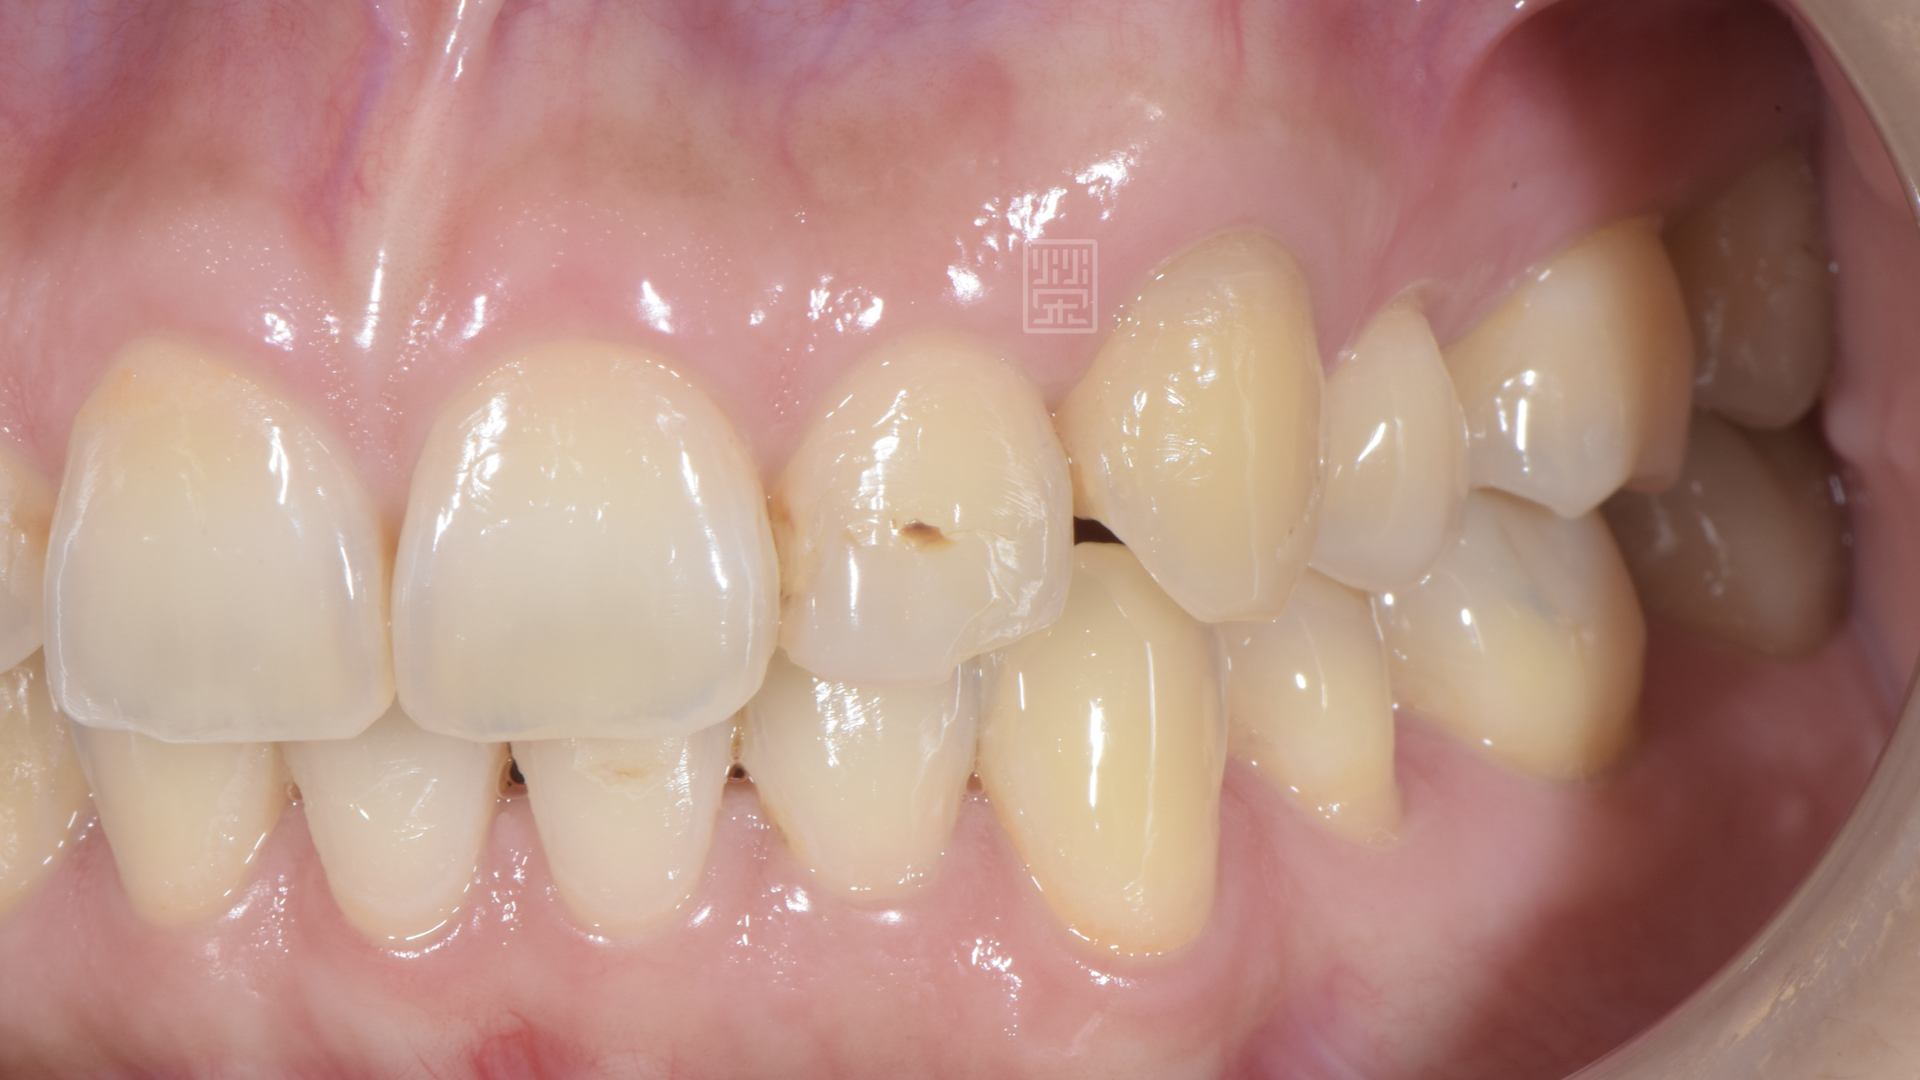

既然已經確定牙齒神經病變壞死,所以將牙髓組織清除,然後做齒內美白,恢復牙齒原本的顏色。

牙齒恢復顏色